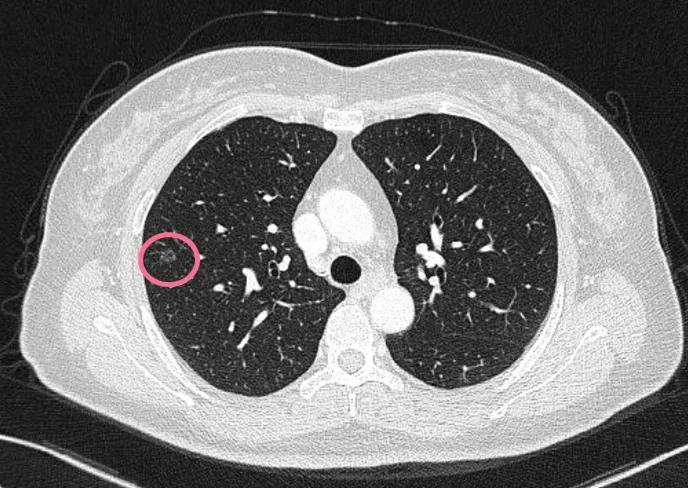

可见是右下肺达近5厘米的肿块,并上叶磨玻璃结节以及斜裂、水平裂多发微小结节。影像是如何的呢?

到底该如何考虑?下一步该如何决策?我的意见是:右下叶红色圈起来的考虑是肺癌,浸润性腺癌可能性大;右上叶磨玻璃结节粉色圈起来的考虑原位癌或不典型增生可能性大;绿色圈起来的基本上是叶裂处,从密度来看更像良性,但因为有右下叶的病灶在,也可能是种植转移,但术前较难确定。PET-CT可以考虑,但也有假阴性或假阳性。个人意见是如果没有远处其他确切转移,建议胸腔镜下探查,如果微小实性结节非转移性,则右下肺癌仍能手术的。如果真若是转移,也可取行病理依据,并送基因检测与免疫组化等检查,而单孔胸腔镜下探查下创伤小,恢复快,当然若不是转移,顺便镜下行右下叶切除并清扫淋巴结就行。